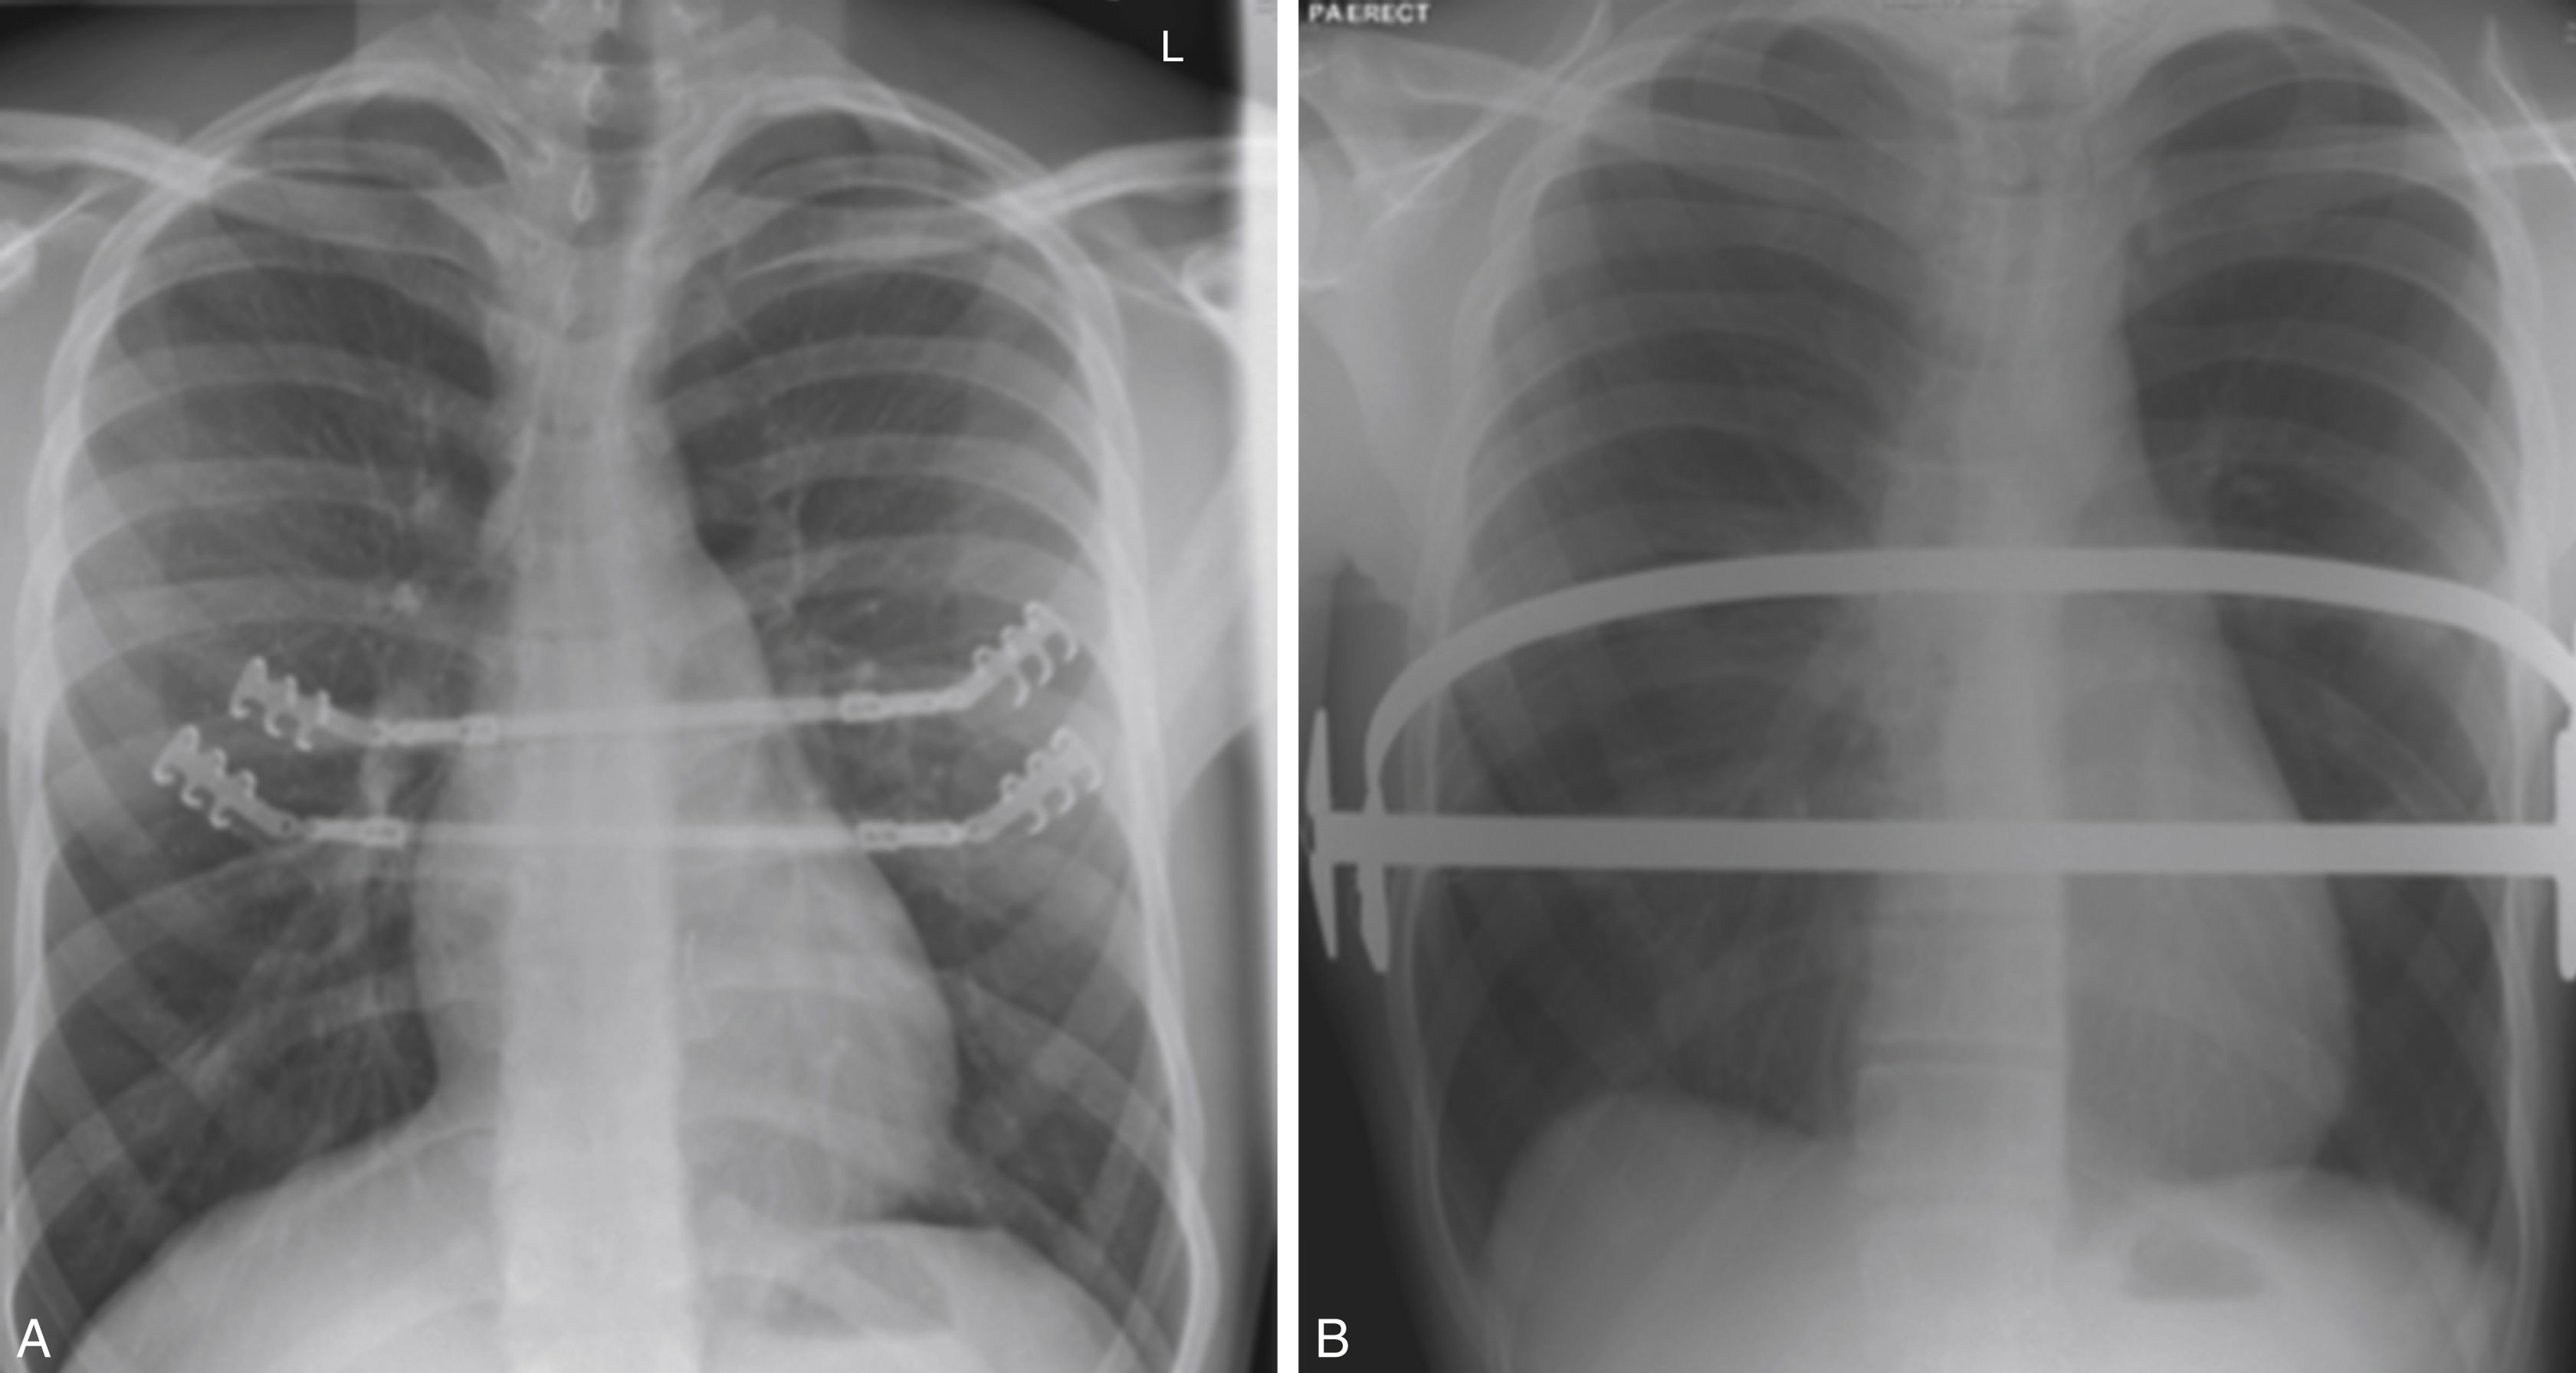

Our method of repair is based on that of Ravitch, but with the addition of any of the metal implants that we may have to consider, if needed for further stability. Chest wall stabilization using the Strasbourg Thorax Osteosyntheses System (STRATOS, MedXpertGmbH, Heitersheim, Germany) of costal bars ( Fig. 39.3A ) was considered very effective, till we recently reported on a high fracture rate of these bars.

Fig. 39.3

(A) STRATOS bars in place for stability following repair of pectus carinatum. (B) Two Nuss bars in situ following repair of pectus excavatum.

The two lateral skin incisions are made, and the subcutaneous plane is developed to the marked point beneath the nipples at the level of where the bar will lie. These will be the points at which the bar will exit the chest wall on either side. Then, the thoracoscope is introduced into the right pleura through a port placed either just beneath or into the lateral skin incision. Carbon dioxide insufflation permits exposure. Next, the bar introducer creates a subcutaneous tunnel from the skin incision to the point of entry into the chest. Entry through the chest wall is observed via thoracoscopy. The introducer is passed to the pleural cavity on the other side, anterior to the pericardium under direct vision. It is guided through the chest wall. Once safely out of the skin, it is tied by umbilical tape to a molded Nuss bar of appropriate size. As the introducer is removed, the bar is carried with it into the chest. The bar is then finally flipped with a specially-designed flipper and secured to the chest wall by bilateral stabilizers secured to it by steel wire (see Fig. 39.3B ).

Following the procedure, the patient is extubated on table and a chest radiograph is taken immediately to check for pneumothoraces and bar position.

Once on the ward, the patient is observed in the high dependency unit for the duration of the epidural catheter – usually 4–5 days. Adequate analgesia is very important here once the epidural is removed. Mobilization aided by physiotherapy is the final step before discharge. A final posteroanterior and lateral chest radiograph check the bar position.